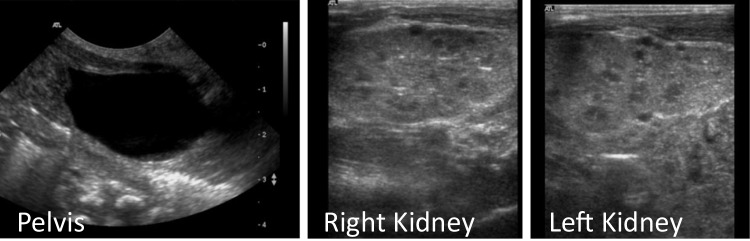

背景:先天性肾病综合征(CNS)是一种罕见的疾病,由足细胞功能和肾小球狭缝隔膜完整性所必需的基因突变引起,包括CRB2(碎屑细胞极性复合物组分2)。CRB2突变与局灶节段性肾小球硬化和囊性肾病伴心室肿大有关,但其完整表型谱尚不清楚。我们描述了纯合子CRB2突变的同卵双胞胎的临床过程,突出了肾移植后的严重并发症。方法:对产前怀疑多囊肾病后诊断为CNS的双胞胎进行随访和全程管理。最初的外显子组测序结果为阴性,但随后的全外显子组测序显示为纯合子CRB2变体。结果:两名双胞胎均出现中枢神经系统,需要加强支持治疗。其他发现包括脑异位、心脏受累和发育迟缓。他们都发展为肾衰竭,需要在儿童早期进行血液透析。移植后,第一个双胞胎死于全身性真菌感染,而第二个双胞胎则出现了与免疫失调相关的并发症,包括移植后淋巴细胞增生性疾病(PTLD)、免疫性血小板减少性紫癜(ITP)、多种病毒血症和新生供体特异性抗体(DSA)。结论:本病例扩大了crb2相关疾病的表型谱,突出了管理方面的挑战,并强调了对罕见病进行基因重新分析的必要性。crb2的相关机制有待进一步研究。

Results: Both twins presented with CNS, requiring intensive supportive care. Additional findings included cerebral heterotopia, cardiac involvement, and developmental delay. They both progressed to kidney failure, necessitating hemodialysis in early childhood. Post-transplant, the first twin succumbed to a systemic fungal infection, while the second developed complications linked to immune dysregulation, including post-transplant lymphoproliferative disease (PTLD), immune thrombocytopenic purpura (ITP), multiple viremias, and de novo donor-specific antibodies (DSA).